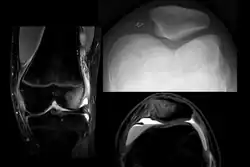

![]() | |

| X-ray showing a patellar dislocation, with the patella out to the side. | |

On X-ray, with skyline projections, dislocations are readily diagnosed. In borderline cases of subluxation, the following measurements can be helpful: